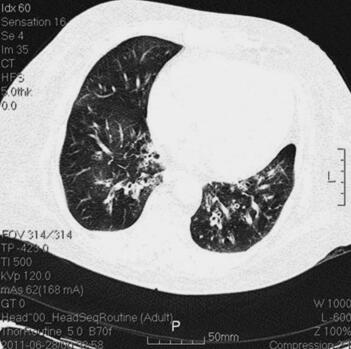

体格检查:P 85次/分,R 12次/分(机械通气),BP 121/61mmHg(多巴胺针剂维持下),T 37.3℃,SPO2 98%。神志清,精神差,气管居中,口插管在位,机械通气,颈静脉无怒张,桶状胸,两肺呼吸音粗,可闻及大量湿啰音及干啰音,心率85次/分,窦性,律齐,双下肢无明显水肿。辅助检查:胸部CT(6月28日)(图1):两肺感染性病变,两下肺支气管扩张症伴感染。心电图(6月28日):窦性心律,T波改变。血常规(6月28日):WBC 13.5×109/L,N 66.3%,Hb 145g/L;CRP(6月28日)3.8mg/L,PCT(6月28日)5.49ng/ml。

图1 胸部CT(6月28日):两肺感染性病变,两下肺支气管扩张症伴感染